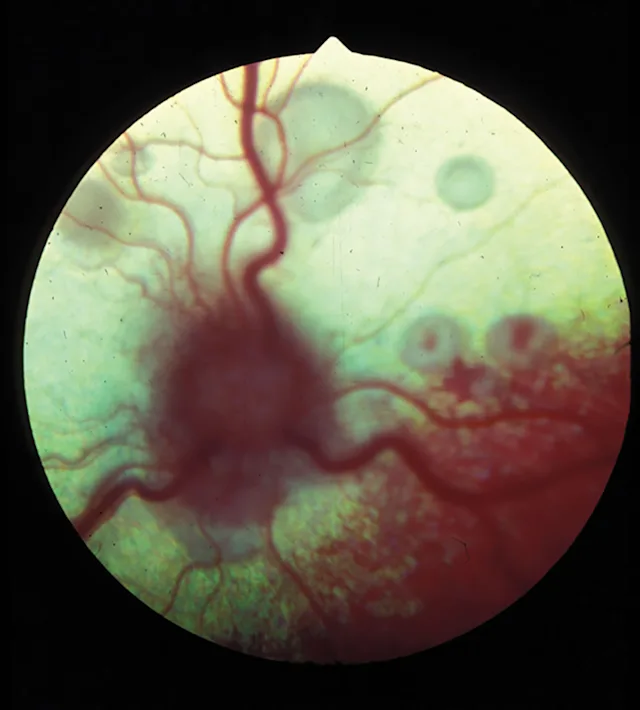

Figure 1.

Active feline chorioretinitis and optic neuritis secondary to systemic cryptococcosis. Multifocal areas of subretinal and peripapillary edema elevate the retina and blur the underlying tapetum.

Chorioretinitis appears clinically as a color change or loss of clarity of tissues on fundic examination. With active chorioretinitis, the addition of fluid, protein, and cells within the retina and subretinal tissues will obscure the tapetum or pigment of the choroid (hyporeflective) and may elevate or detach the retina and blur the image. Vascular involvement may result in perivascular cuffing, vasculitis, hemorrhage, and exudate (Figures 1–7). With active chorioretinitis, anterior segment involvement is common, resulting in aqueous flare, miosis, hypopyon, keratic precipitates, cataract, corneal edema, and intraocular pressure (IOP) changes. With chronicity, chorioretinitis leads to focal or diffuse retinal degeneration, tapetal hyperreflectivity, depigmentation, hyperpigmentation, and vascular attenuation (Figures 8–11).